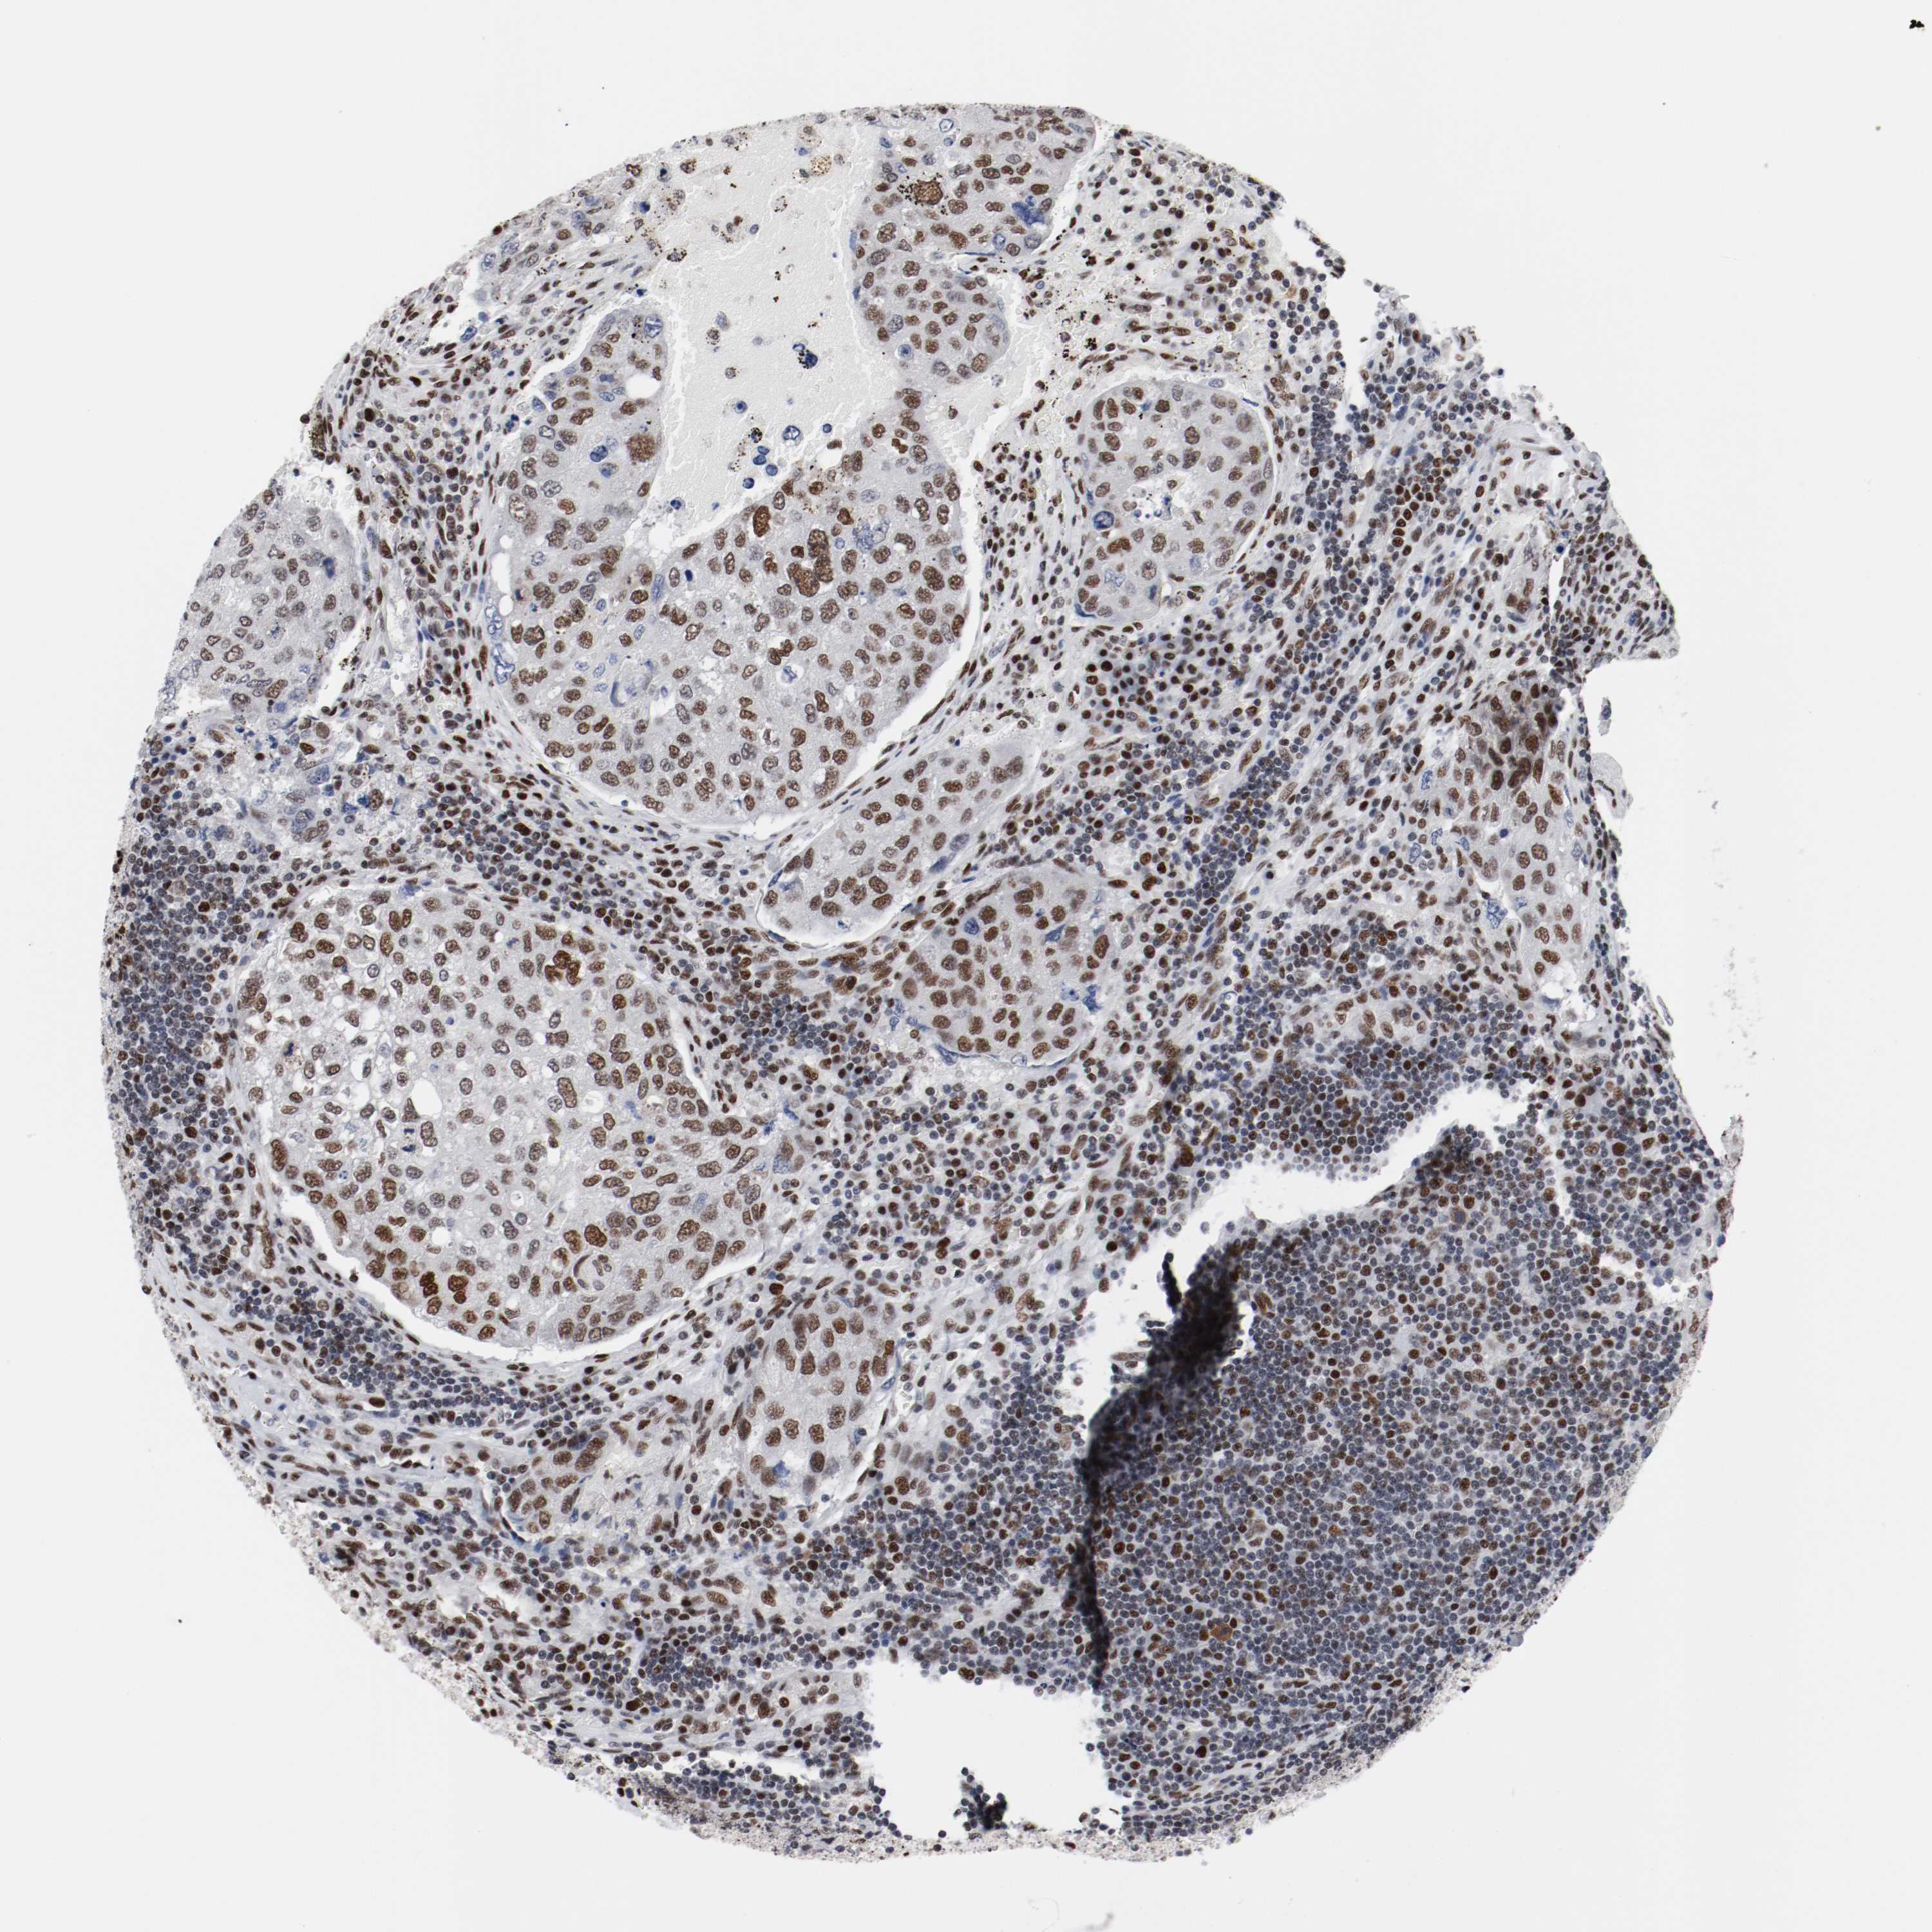

UROTHELIAL CANCER - Protein expressioni

A mouse-over function shows sample information and annotation data. Click on an image to view it in a full screen mode. Samples can be filtered based on level of antibody staining by selecting one or several of the following categories: high, medium, low and not detected. The assay and annotation is described here.

Antibody stainingi

Antibody staining in the annotated cell types in the current human tissue is reported as not detected, low, medium, or high, based on conventional immunohistochemistry profiling in selected tissues. This score is based on the combination of the staining intensity and fraction of stained cells.

Each image is clickable and will lead to virtual microscopy that enables deeper exploration of all samples and also displays staining intensity scores, fraction scores and subcellular localization as well as patient and tissue information for each sample.

Antibody HPA004807

Antibody HPA007114

Staining

High

Medium

Low

Not detected

Intensity

Strong

Moderate

Weak

Negative

Quantity

>75%

75%-25%

<25%

None

Location

Nuclear

Cytoplasmic/membranous

Cytoplasmic/membranous,nuclear

Urothelial carcinoma, High grade

Urothelial carcinoma, Low grade